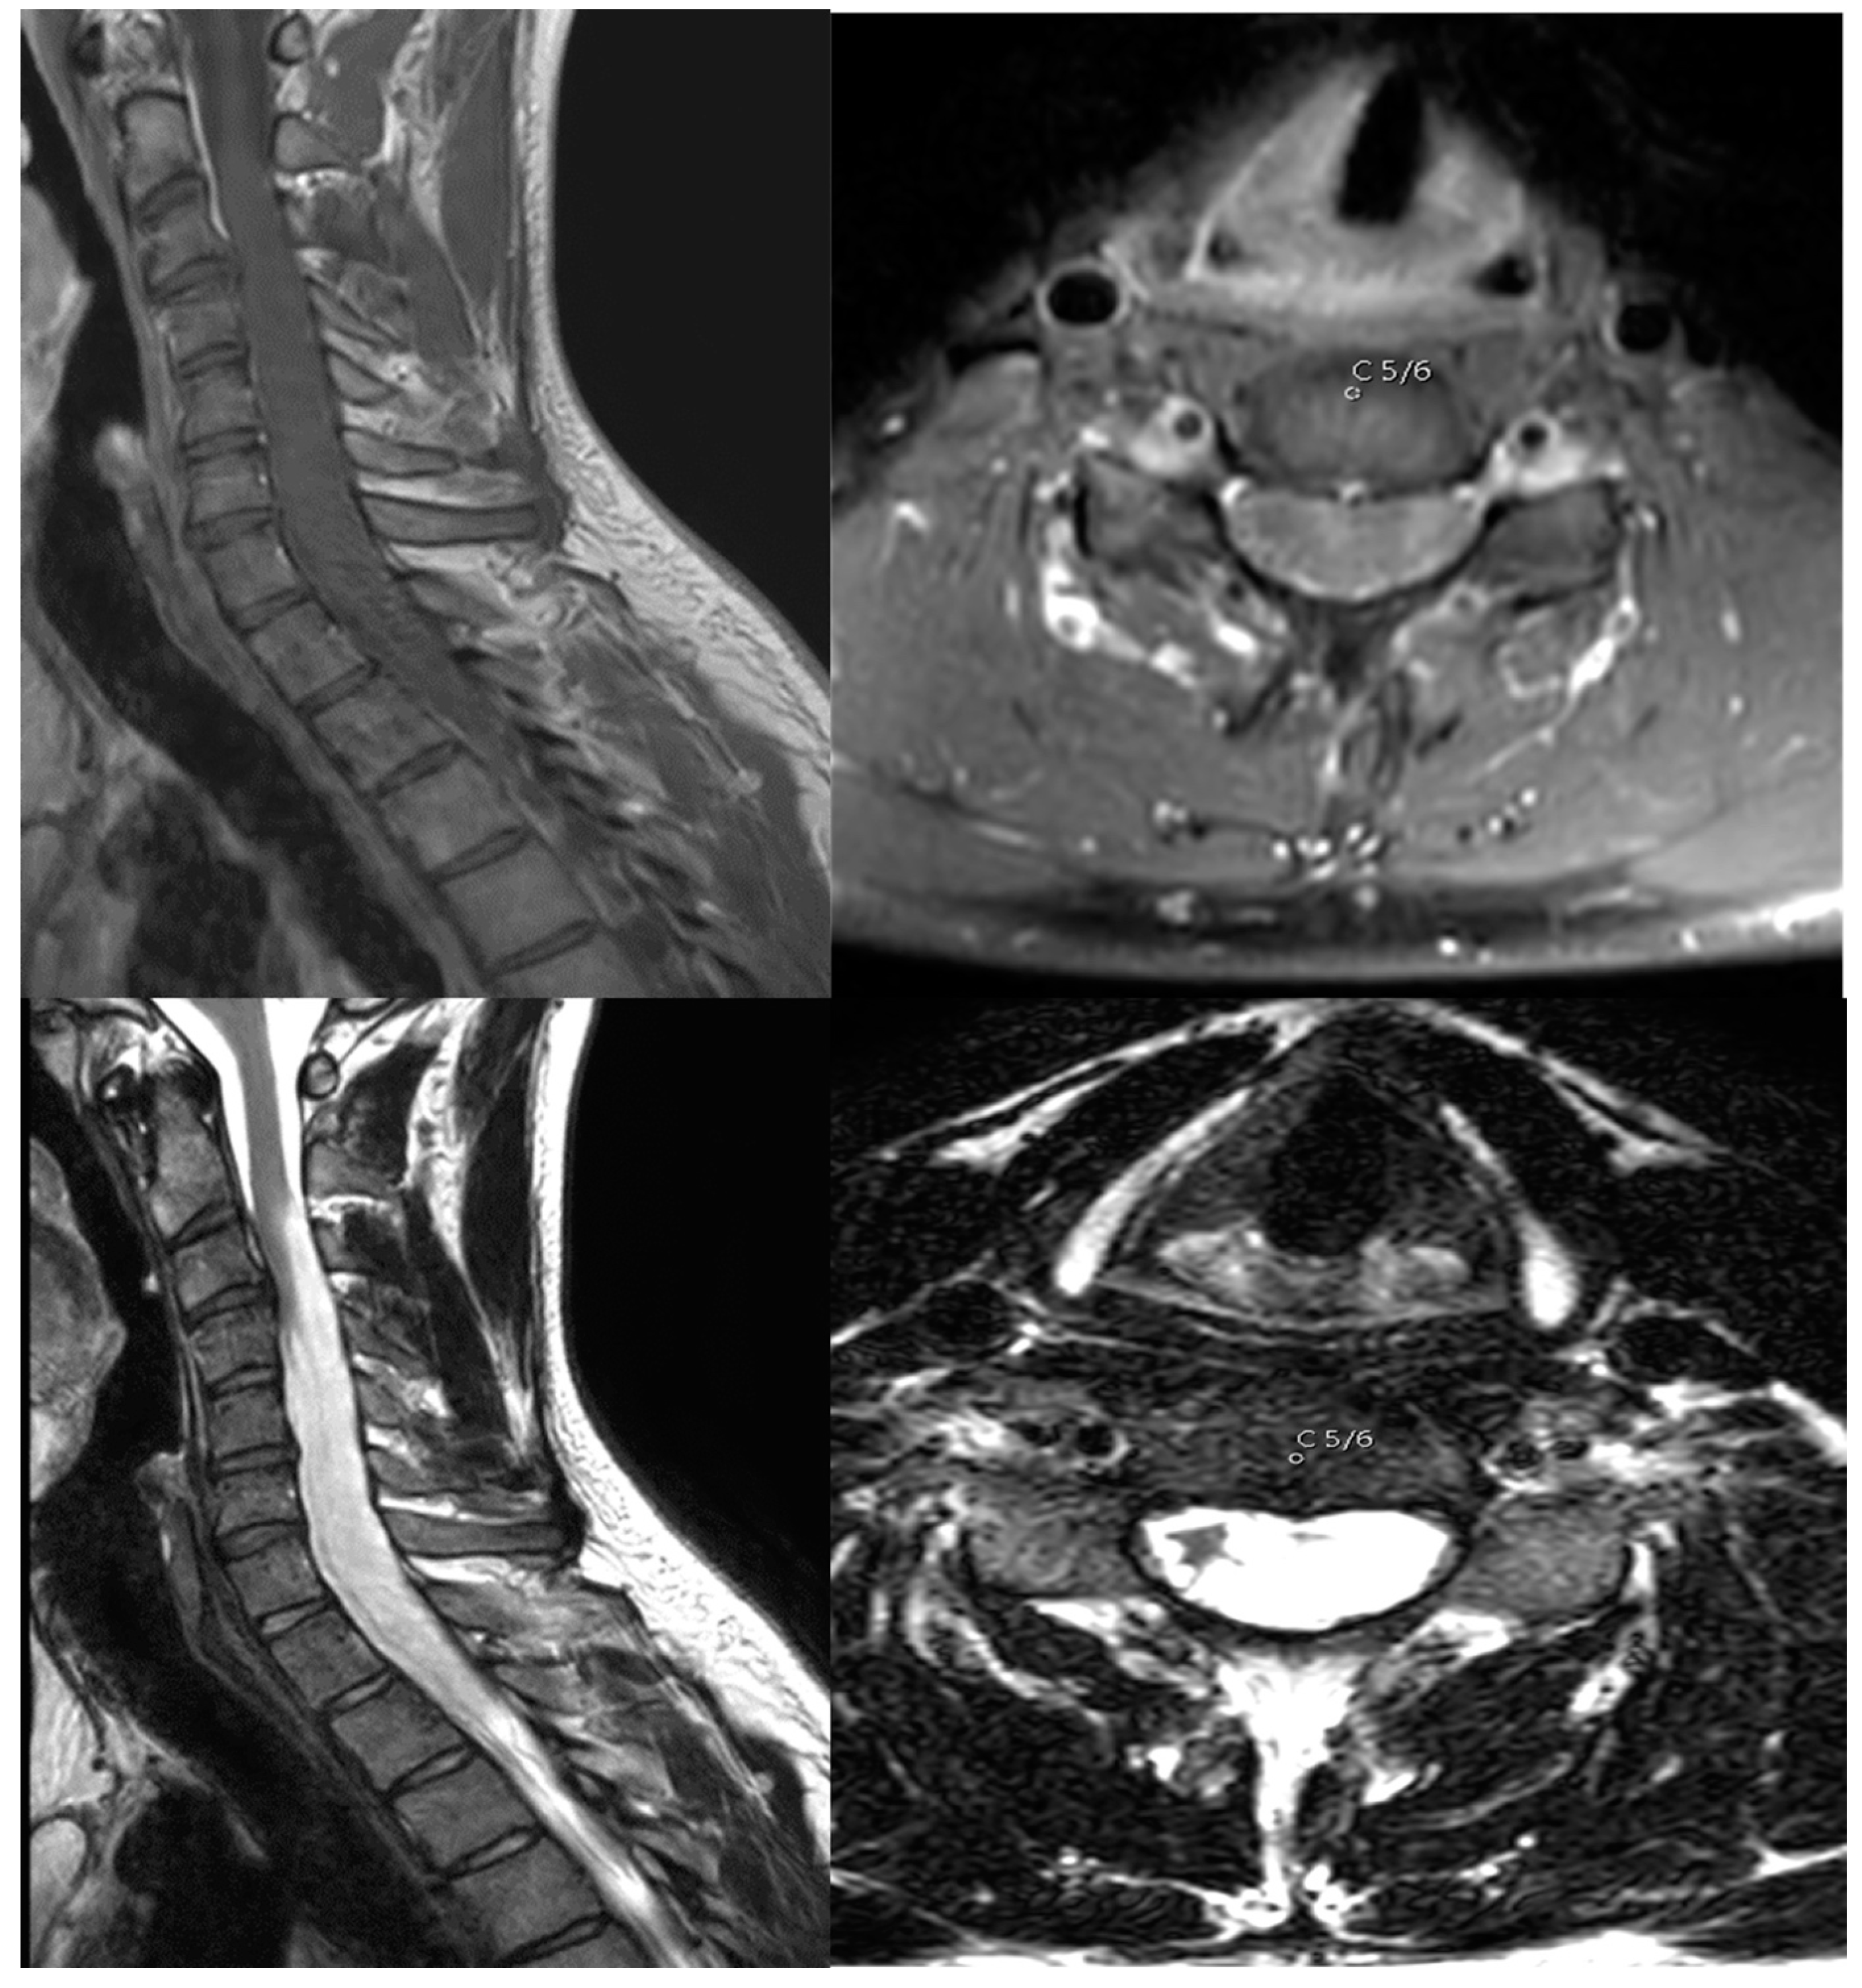

A young male patient initially presented in early 2019 with a distal finger flexor paresis on the left hand, hypesthesia along the C8 dermatome, and an MRC 4/5 paresis in the left leg. Together with the myelopathy, the symptoms progressed over a time span of 10 years before consultation at our outpatient care center (mMS Grade II upon first visit). A contrast-enhanced MRI scan showing an intramedullary lesion reaching from C2 to Th3 was shown (Figure 1).

Figure 1. T1-MRI scan with contrast enhancement (upper image) and T2-MRI scan (lower image) showing the extent of the lesion before surgery. The axial images depict level C5/6.